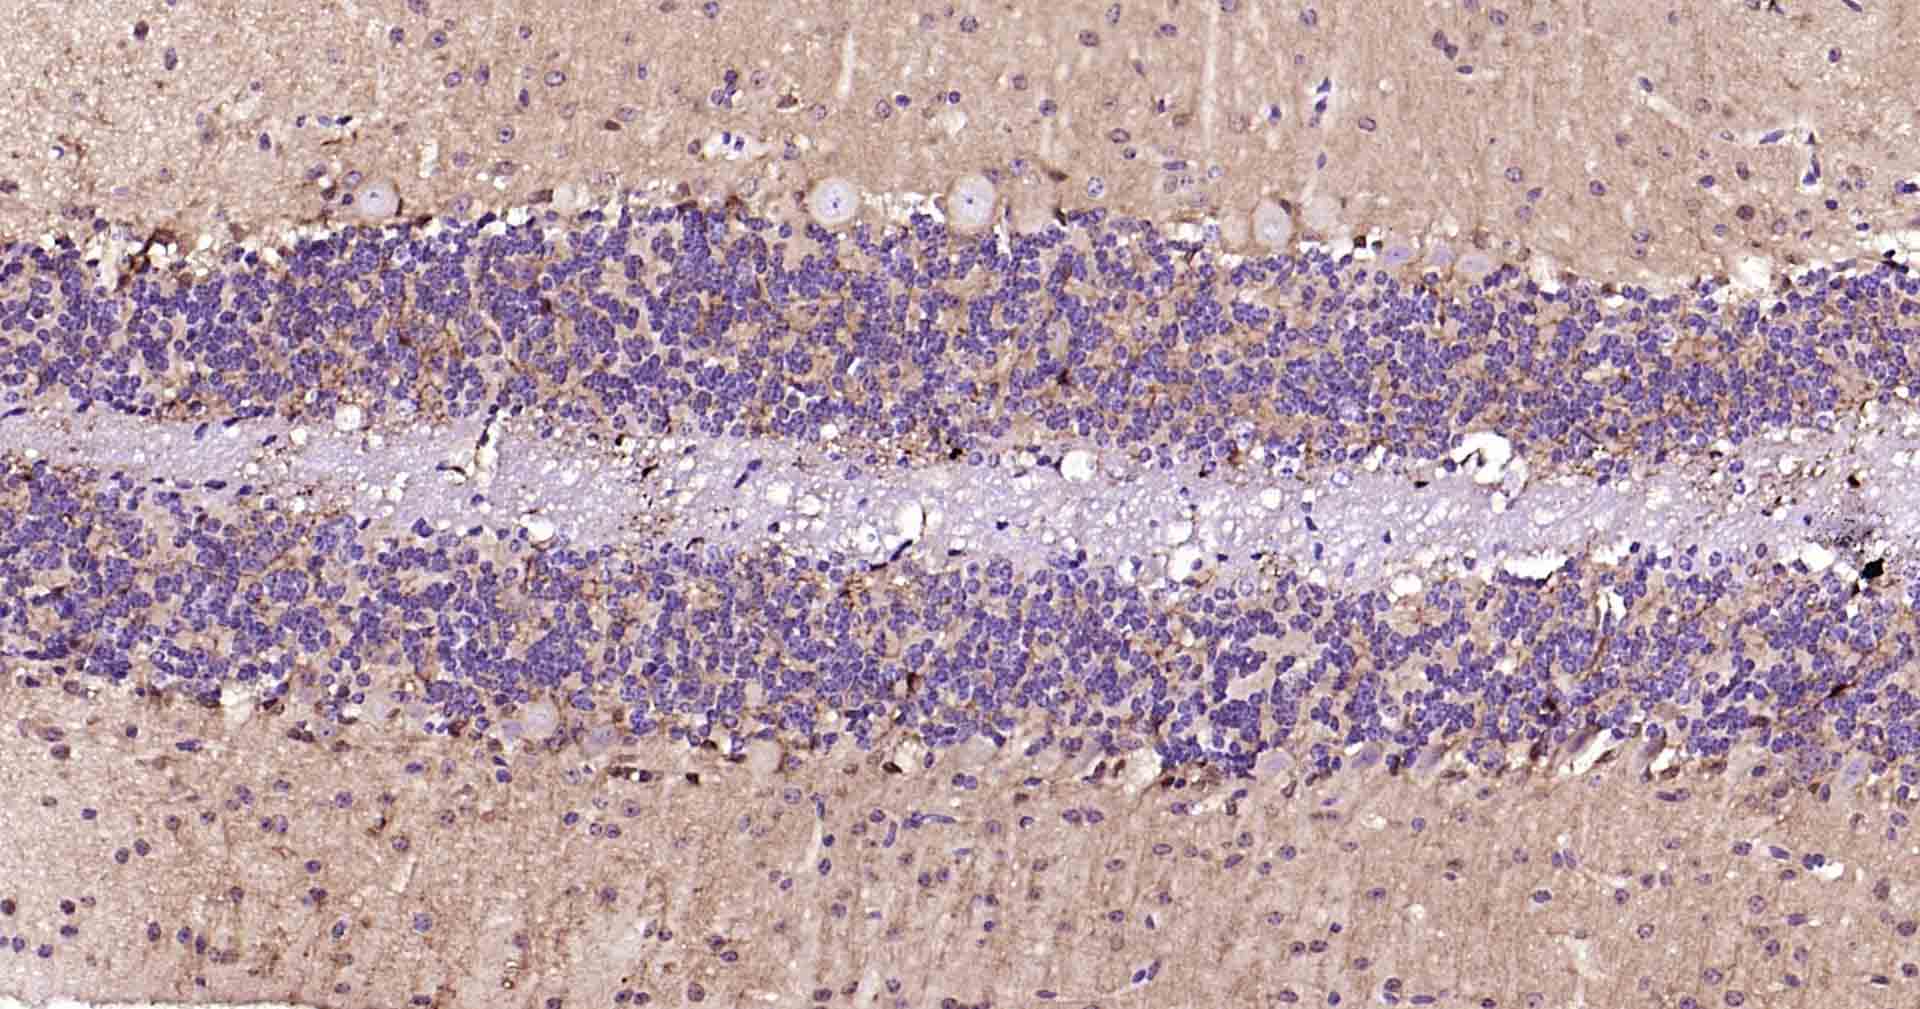

Paraformaldehyde-fixed, paraffin embedded Human Cerebellum; Antigen retrieval by boiling in sodium citrate buffer (pH6.0) for 15 min; Antibody incubation with NSE Monoclonal Antibody, Unconjugated(bsm-60786R) at 1:200 overnight at 4°C, followed by conjugation to the SP Kit (Rabbit, SP-0023) and DAB (C-0010) staining.